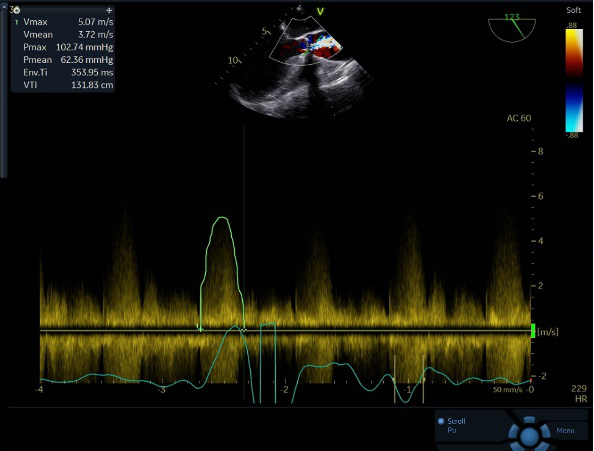

手术即刻超声测量,主动脉瓣工作良好,无反流,与术前超声测量数据对比,流速、跨瓣压差得到有效改善。

超声评估

术前、术后血流动力学评估

患者71岁女性,入院超声检查显示主动脉瓣重度狭窄并轻度关闭不全、瓣叶增厚、回声增强,活动受限峰值流速473cm/s,平均压差60mmHg,最大压差90mmHg,瓣口面积约0.27cm2。左心增大,LVEF 37%,升主动脉增大。